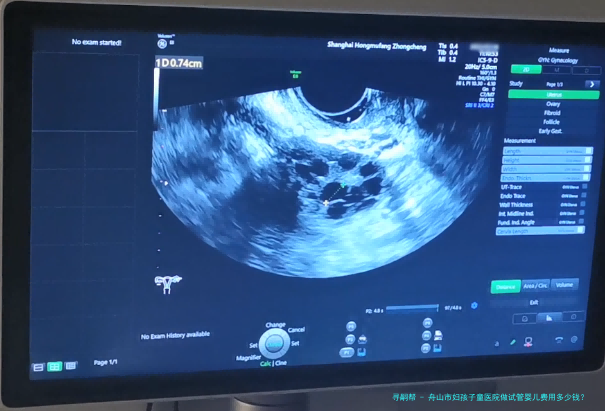

希望拥有本人的宝宝,但因为诸多原因无从自然受孕,试管婴儿就成为无数家庭的曙光。舟山市作为一个享有许多优质医疗机构之处,也提供着完备的试管婴儿服务。哪样舟山市妇孩子童医院做试管婴儿费用多少钱?成功率怎样呢?

舟山市妇孩子童医院是一家集医疗、教学、科研为一体的综合性三级妇产专科医院。医院成立于1958年,拥有先进的医疗配备和专业的医护集体,专心于为女性及儿童提供优质的医护服务。医院一向坚持“以人为核心”的观念,承继“精良、规范、高成效”的服务宗旨,为患者提供全面性、个体化的服务。

舟山市妇孩子童医院的试管婴儿成功率在百分之六十五左右,详细的成功率还会根据患者的身体状态、年龄等因素有所差异。